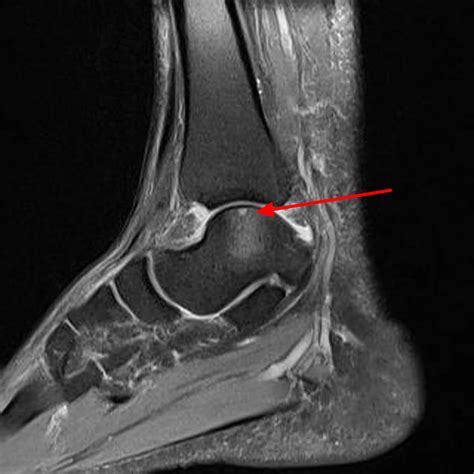

• Imaging Tests: Imaging tests, such as X-rays, MRI, or CT scans, are used to visualize the bone and cartilage within the ankle joint. These tests can help identify the location and extent of the lesion.

Imaging tests are particularly important in diagnosing Osteochondritis Dissecans Ankle, as they can provide detailed information about the condition of the bone and cartilage.